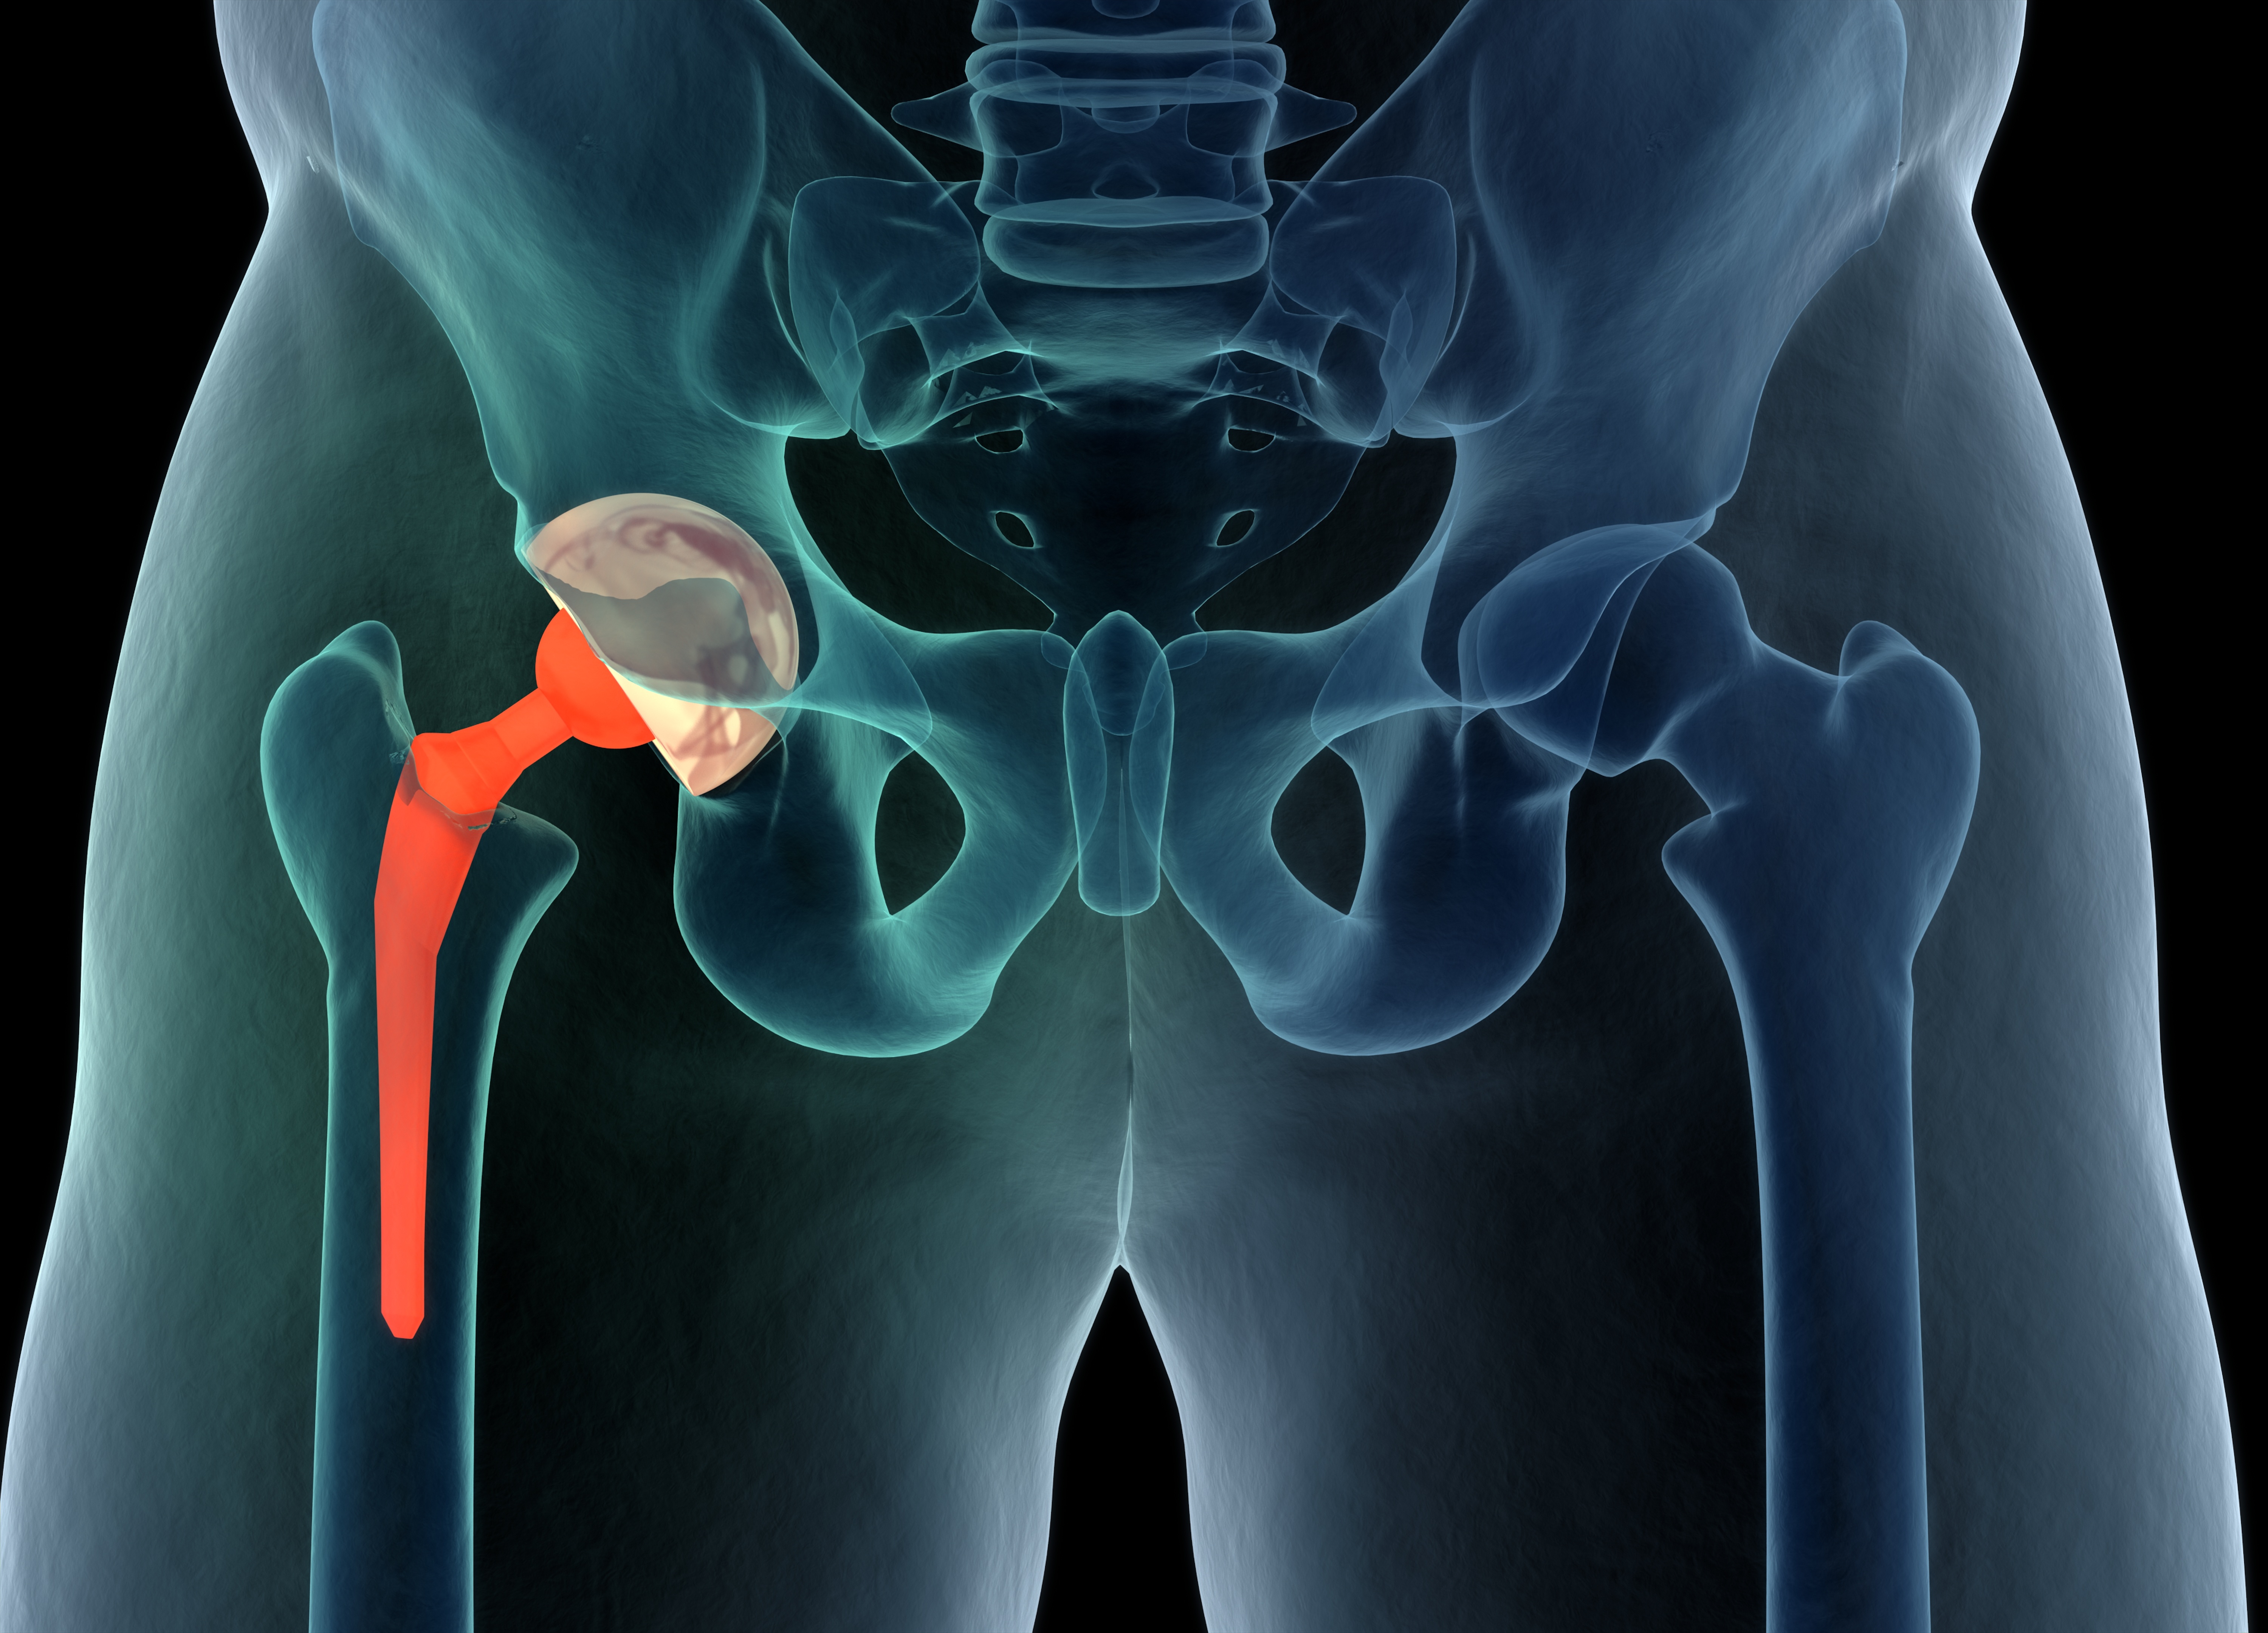

és csípőprotetika

A revíziók a korábban beültetett protézisek körüli ismételt műtéteket jelentik.

A revíziókat fertőzések, lazulások, ficamok és törések miatt kell végezni a leggyakrabban. Általában ezen beavatkozások jóval összetettebb műtétek, melyek nagy vérvesztéssel, nagy műtét körüli megterheléssel és hosszabb lábadozással járnak, a reviziós műtétek utáni funkció pedig elmarad az első műtét utáni funkcióhoz képest.